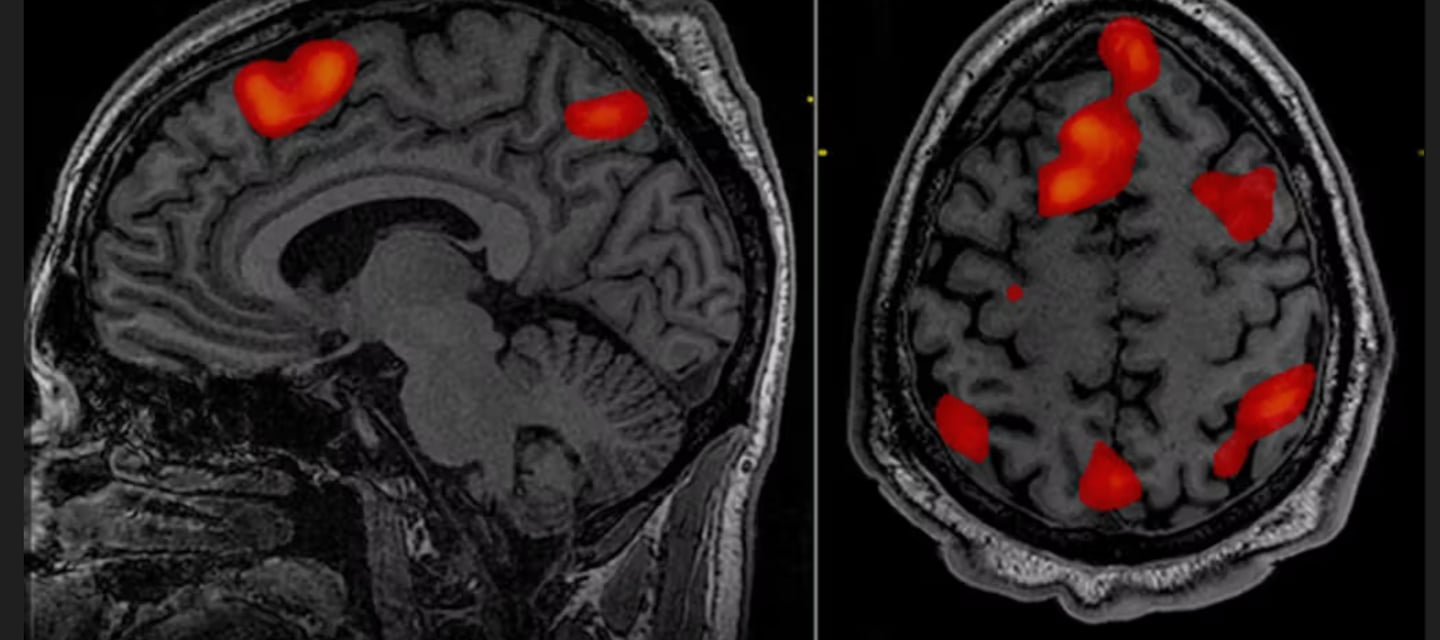

Functional magnetic resonance imaging

Functional magnetic resonance imaging (IMRI) scanners were used to compare the brain activities of clinically depressed and healthy people. By analysing both sets of scans, the researchers discovered people with depression have a particular brain net- work which appears to be nearly twice as big as their psychologically healthy counterparts. They suggested depression may be linked to this network and could be a new target for treatment or a way to prevent it entirely. The identified brain network is called the frontostriatal salience network and it plays a role in processing rewards and deciding what merits attention. 'Having a larger salience network appears to increase the risk for depression,' said Conor Liston, a professor of psychiatry and neuroscience who co-authored the research. Crucially, this study highlights a seismic shift in mainstream medical belief about what causes depressive feelings. This is thought to be because one of the main symptoms of depression is anhedonia - the inability to feel pleasure and enjoy everyday activities. Since the 1980s, psychiatrists have commonly blamed a 'chemical imbalance' in the brain - specifically, a lack of serotonin and drug companies launched a generation of antidepressants that promised to correct this imbalance: namely, the selective serotonin re-uptake inhibitors (SSRIs), such a s Prozac and Zoloft. But these pills a re-increasingly shadowed by serious concerns about their usefulness, and their debilitating potential side - effects, including weight gain, sexual dysfunction, and an increased risk of suicidal thoughts. Two years ago, the Beyond Pills All-Party Parliamentary Group which included nine professors of medicine and psychology, published an open letter in the BMJ claiming that rigorous analyses show SSRIs 'have no clinically meaningful benefit beyond placebo for all but the most severely depressed patients'. What's more, studies show the drugs can cause serious dependency a n d crippling withdrawal symptom.